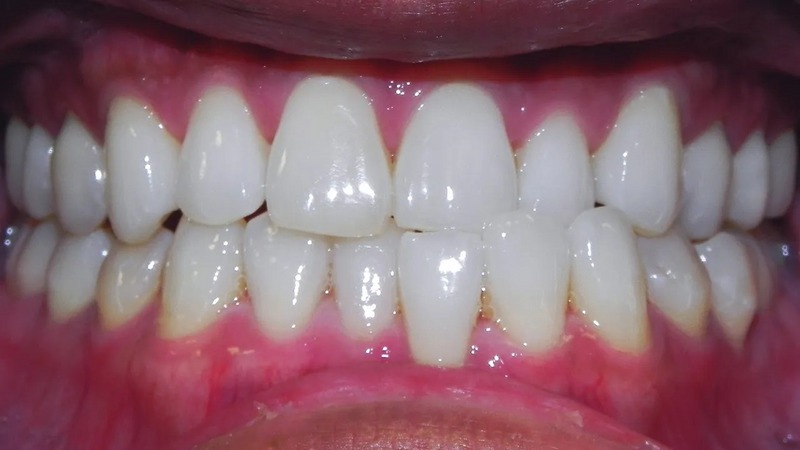

انواع کراس بایت (کراس بایت دو طرفه)

کراس بایت دو طرفه